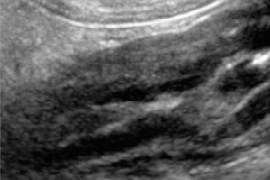

Dr. Le Roux graduated from the Veterinary School of Nantes, France, in 2006. After a rotating small animal internship in Toulouse and a radiology internship in Belgium, he completed a radiology residency program at the Veterinary School of Louisiana State University in 2013. Dr. Le Roux became a Diplomate of the European College of Veterinary Diagnostic Imaging in 2012, and a Diplomate of the American College of Veterinary Radiology in 2014. During his residency at LSU, he also started a Master of Science about histological and ultrasonographic correlation of small intestinal layering in dogs, that he completed in 2015. Dr. Le Roux has a special interest in gastrointestinal imaging in dogs and cats.